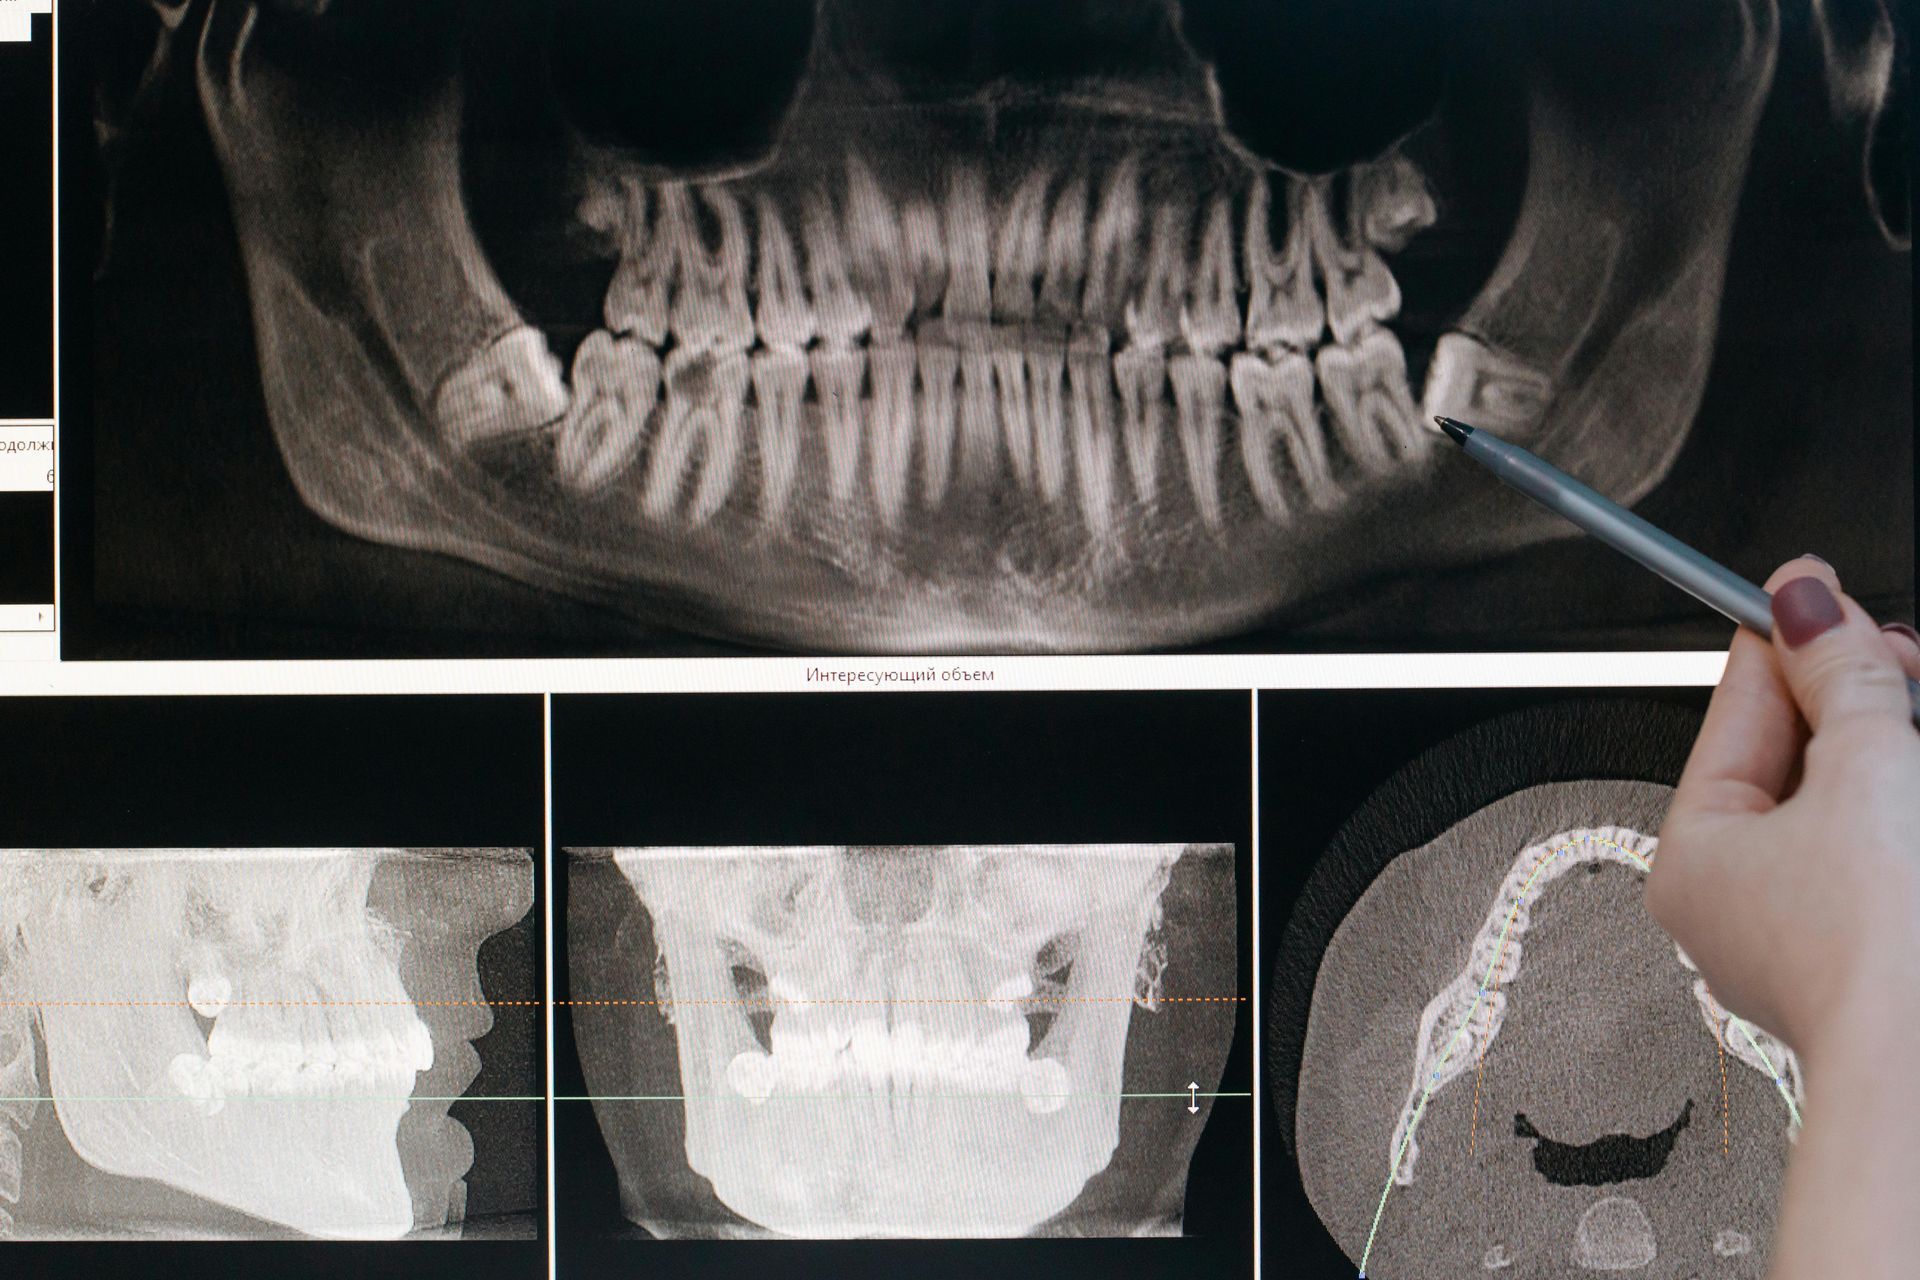

is a more advanced dental procedure used for teeth that cannot be removed easily. This includes teeth that are impacted, broken below the gum line, or surrounded by dense bone.

- Complex Dental Procedures affecting bone or nerves

- Surgical Tooth Removal may involve cutting the gum or bone